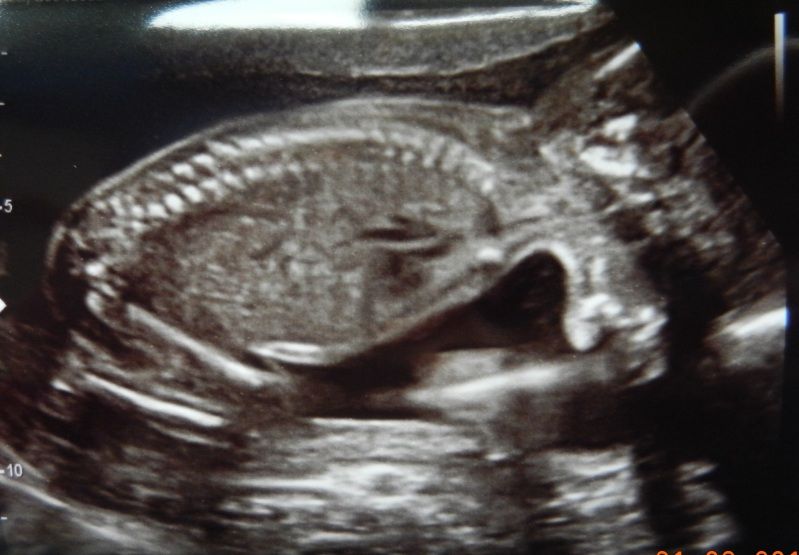

Mooie ruggengraatje: